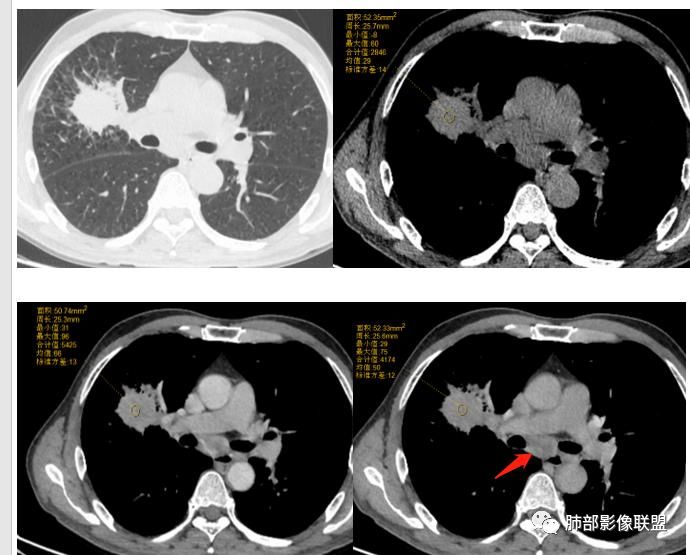

肺肉瘤样癌影像表现

影像表现缺乏特异性,CT最常见的表现是位于周围肺野的实质性肿块,病变部位以上叶多见,常位于胸膜下;

因为病灶有上皮成分和间叶成分,所以兼具肺癌和肺肉瘤的影像学特征,

1.具有肉瘤的特性:肿瘤体积一般较大,直径约大于5cm,边缘清楚、光整,由于肿瘤生长迅速,可见大片坏死,坏死边界清楚;常见支气管推移。

2.具有癌些特性:如分叶、短毛刺、空洞,但是钙化及胸膜凹陷征少见,病灶往往是直接侵犯胸膜,可以远处转移,肺门及纵隔淋巴结可明显肿大;

3.强化方式:增强后病灶以环状强化为主,病灶周边多以癌组织为主,血供丰富,病灶中心区则以肉瘤成分为主,血供较差,易出现粘液样变性、坏死、出血,坏死边界清楚,所以增强CT对PSC与普通型肺癌有一定的鉴别价值。

(中央型PSC肿块常位于肺门处,肿块多较大,边界较光整,伴有阻塞性肺炎或肺不张,与常见类型肺癌不易鉴别。)

病例小结

1.本病例结合病理结果及影像综合分析,应该符合肉瘤样癌,上皮成分是腺癌为主;肿块的边缘毛刺、分叶及周围癌型淋巴管炎征象有符合腺癌的影像表现之处。

2.肿块巨大局部边缘膨隆、光整,坏死较彻底;明显跨叶生长(途经发育不全叶间裂或肺门,注意患者没有胸水),支气管阻塞伴推移等,这些更符合肉瘤的特性。

3.坏死区边界较清楚(皮囊样),环形强化明显,病灶内血管穿行等,都不符合我们常见的鳞癌。

4.肺肉瘤虽然也是肿块巨大,呈大片状坏死,但是边缘光整圆隆,没有分叶、毛刺征象,较少出现肺门及纵隔淋巴结转移。